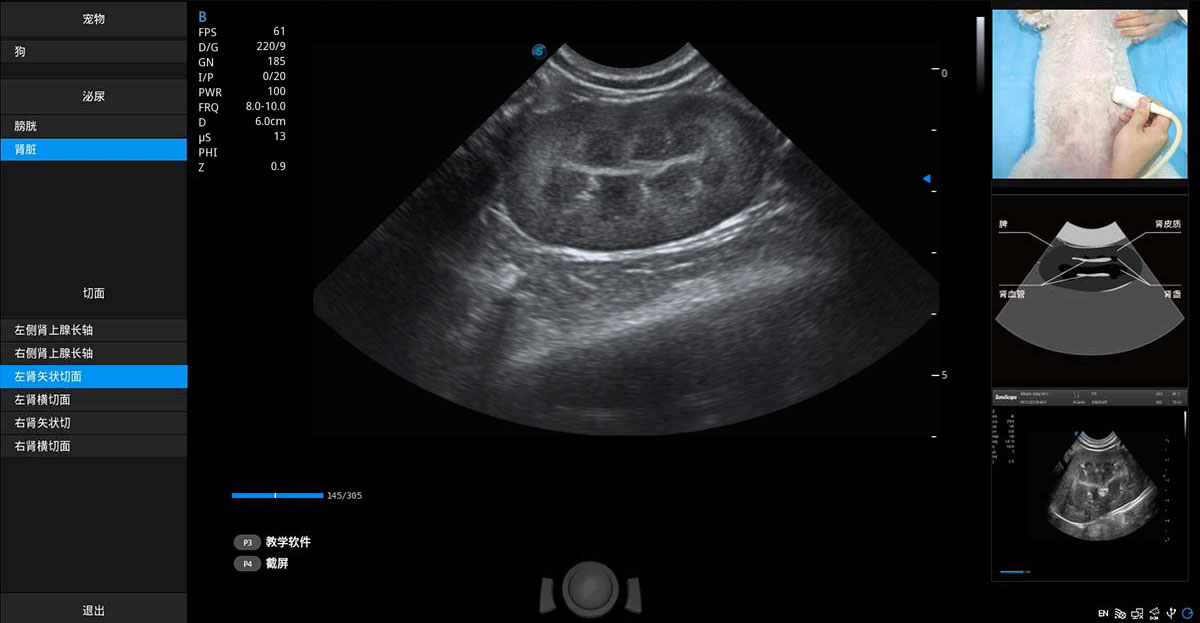

提供解剖示意圖、標(biāo)準(zhǔn)超聲圖像、掃查手法圖和操作者實(shí)時(shí)檢查圖像,指導(dǎo)操作者進(jìn)行標(biāo)準(zhǔn)切面的正確掃查。

ProPet 70專為動物醫(yī)生設(shè)計(jì),對不同的動物體型和生理結(jié)構(gòu)作出了針對性的優(yōu)化。通過動物影像專用軟件,可滿足個性化的應(yīng)用需求,幫助動物醫(yī)生獲得更精確的診斷數(shù)據(jù)。